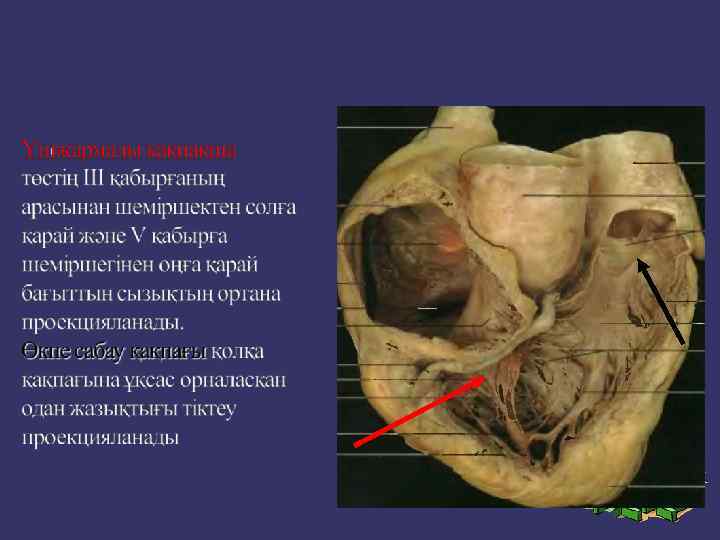

➲ ➲ ➲ Зерттеу барысында жүрек камераларының кеуде қабырғасына жатқызылуын елестетіп алуымыз керек. Оң жақ қарынша жүректің алдыңғы беткейінде орналасады. Бұл камера өкпе артериясымен кеуденің сол және артқы жағында сына тәрізді жазықтықты құрастырады. Оң жақ қарыншаның төменгі бөлігі кеуде денесінің төстің семсер тәрізді өсіндісімен байланысқан жерінен төмендеу орналасқан. Оң жақ қарынша жоғарыға қарай тарылады және III- қабырға мен төстің арасындағы шеміршек деңгейінде өкпе артериясына өтеді. Сол жақ қарынша оң жақ қарыншадан солға және артқа қарай орналасқан. Жүректің алдыңғы беткейінің кіші бөлігін ғана алып жатады. Клиникалық жағынан бұл өте маңызды, өйткені ол жұректің сол жақ бөлігін құрайды және жоғарғы серпілістің негізгі көзі болып табылады. Жоғарғы серпіліс бұл жүректің систола кезінде кеуде қабырғасына соғуын сипатайды және V қабырға арасында болады.

Митральды қақпақ (сол жақ жүрекше - қарыншалық қақпақ) төстің III қабырғамен түйіскен жерінде проекцияланады. Қолқа қақпағы төстің III қабырғаның сол және оң жақтарындағы шеміршектерінің бекіністерінің ортасынан жүргізілген сызықтың ортасында проекцияланады.